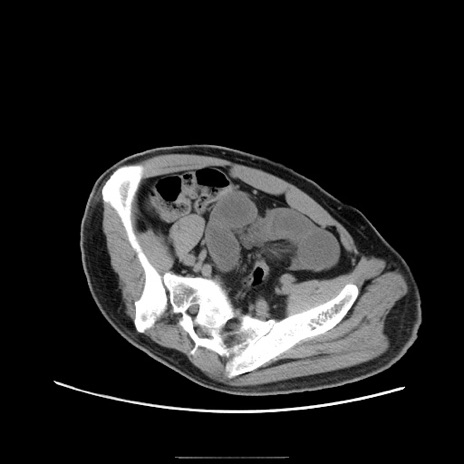

症例22(横断像)

【症例】50歳代男性

【主訴】腹痛

【現病歴】AVMからの被殻出血のため回復期リハ病棟入院中。 本日午後3時頃急に下腹部痛が出現した。

【既往歴】AVM、被殻出血、虫垂炎、高血圧

【身体所見】意識晴明、左半身不全麻痺、会話の理解は良好、36.5°C、腹部:膨隆、全体に板状硬、下腹部正中に圧痛点あり、反跳痛-、筋性防御不明、右下腹部にope scar

【データ】WBC 9400、CRP 0.06